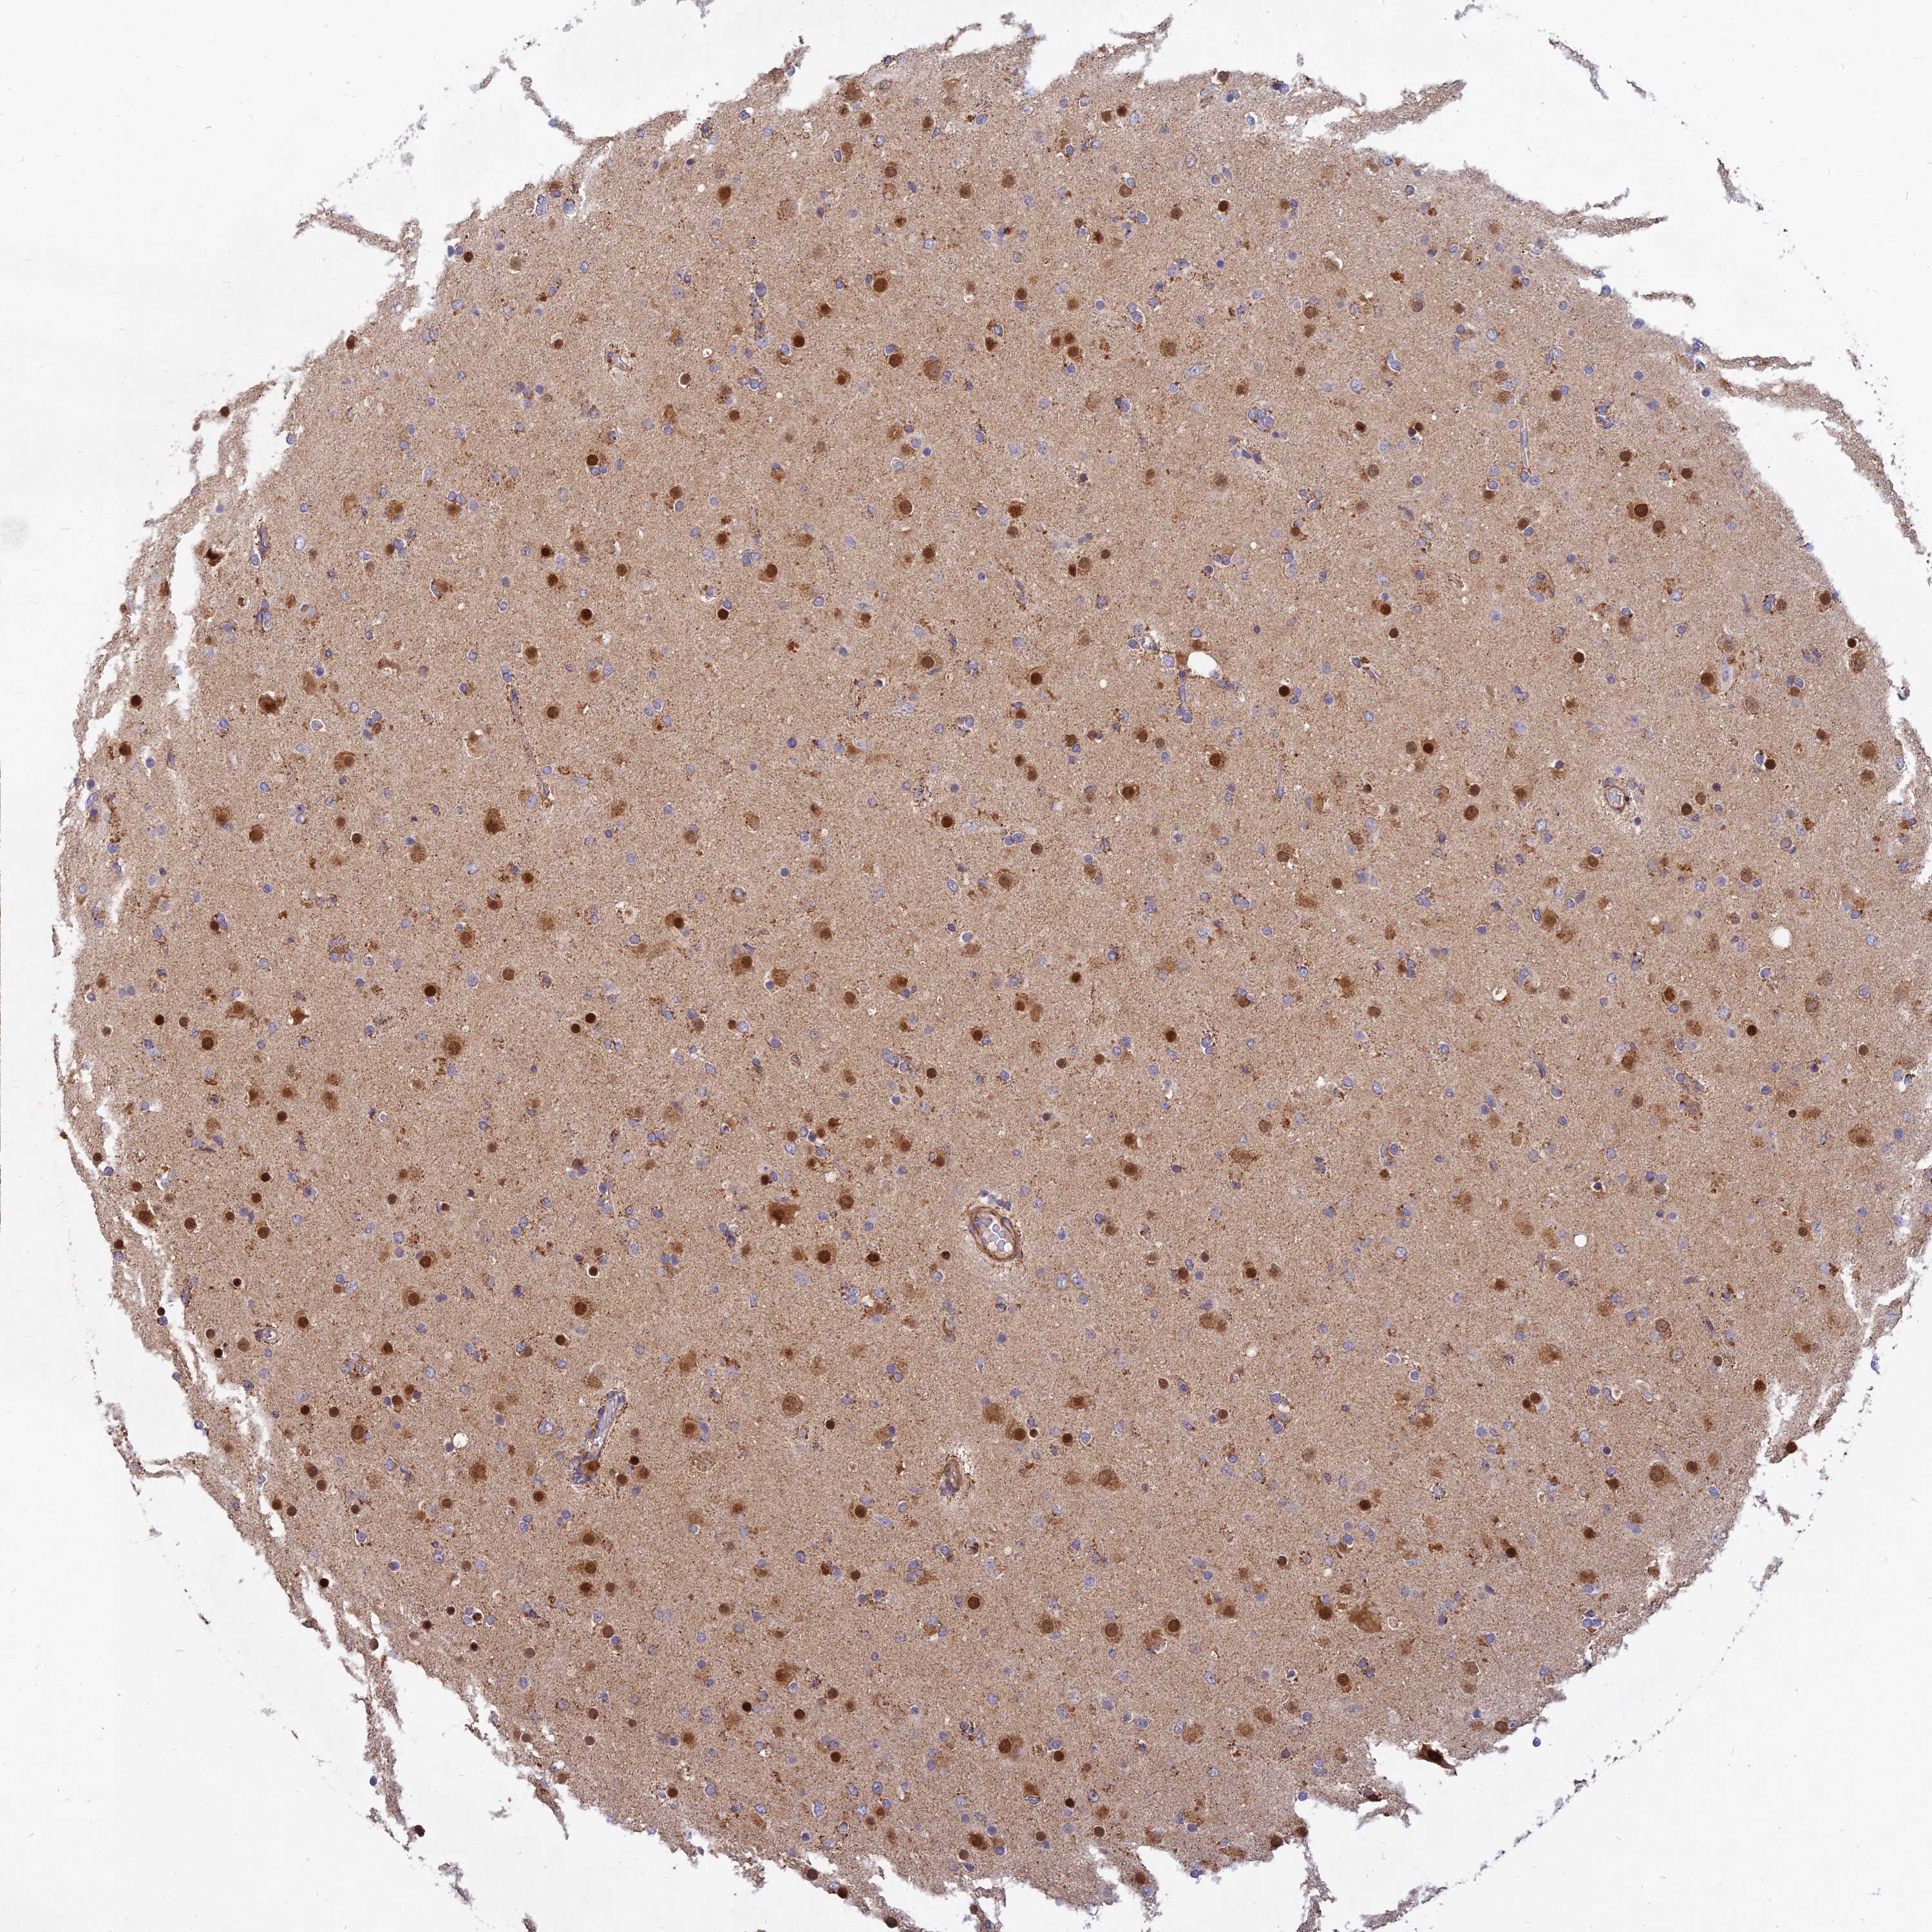

GLIOMA - Protein expressioni

A mouse-over function shows sample information and annotation data. Click on an image to view it in a full screen mode. Samples can be filtered based on level of antibody staining by selecting one or several of the following categories: high, medium, low and not detected. The assay and annotation is described here.

Note that samples used for immunohistochemistry by the Human Protein Atlas do not correspond to samples in the TCGA dataset.

Antibody stainingi

Antibody staining in the annotated cell types in the current human tissue is reported as not detected, low, medium, or high, based on conventional immunohistochemistry profiling in selected tissues. This score is based on the combination of the staining intensity and fraction of stained cells.

Each image is clickable and will lead to virtual microscopy that enables deeper exploration of all samples and also displays staining intensity scores, fraction scores and subcellular localization as well as patient and tissue information for each sample.

Antibody HPA039708

Antibody HPA040038

Staining

High

Medium

Low

Not detected

Intensity

Strong

Moderate

Weak

Negative

Quantity

>75%

75%-25%

<25%

None

Location

Nuclear

Cytoplasmic/membranous

Cytoplasmic/membranous,nuclear

Glioma, malignant, High grade

Glioma, malignant, Low grade